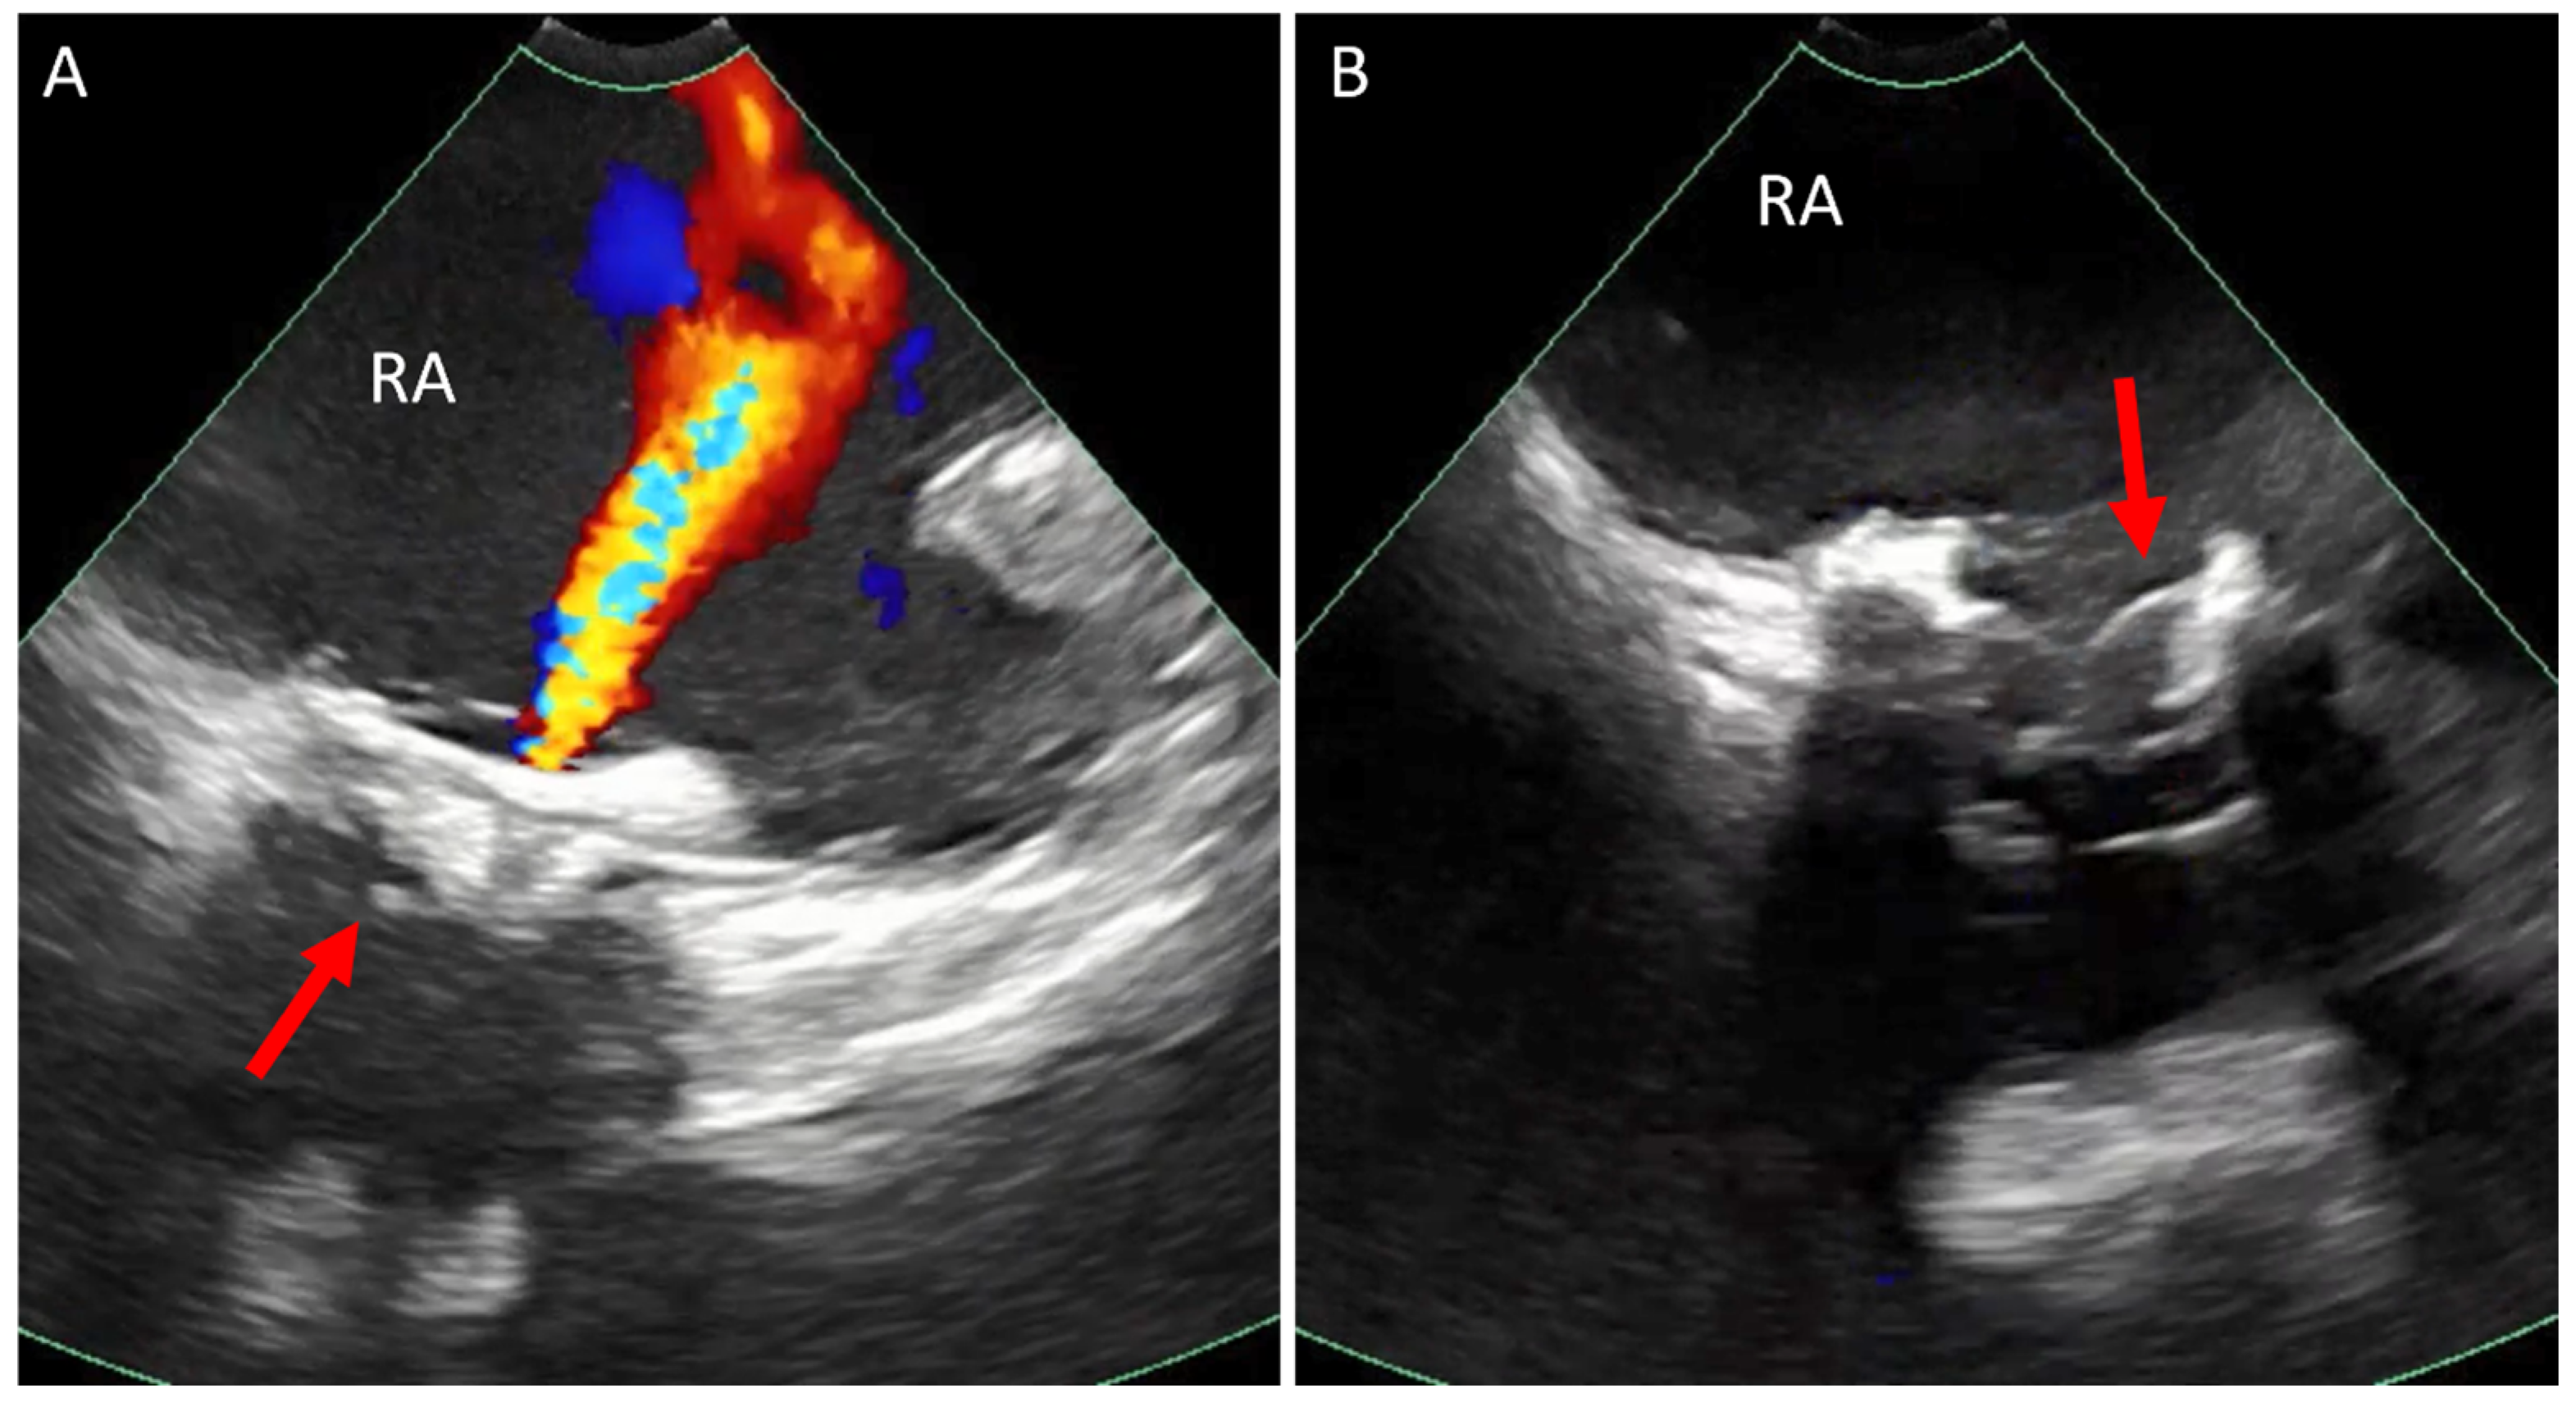

5.1. Paravalve Leak (PVL) Occlusion